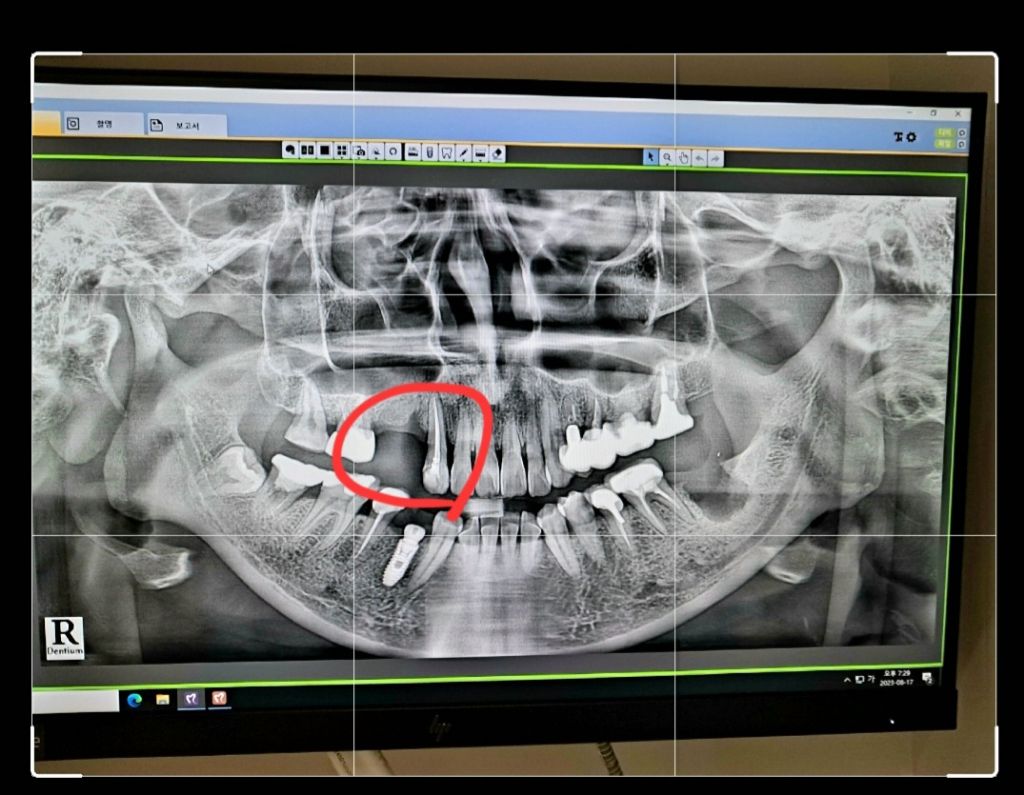

치과. . 임플란트 발치한거 2개있고 이번에 새로 발치할거 1개. 각기 뺀 날짜가 다릅니다. 마지막에 뺀 치아는 뼈가 차 오를때 기다리지 않고 같은날 3개 나사식립 가능한가요?ㆍㆍ 사진상 왼쪽이고 윗니예요. 지금 발치된거 2개는 2,3달전이고 1개는 이번에 발치할 치아거든요. 아무는거보고 식립하나요. 마지막에 뺀 치아는... ? 같은날 식립이 되는지 궁금해요.

아무는거봐서 식립하나요. 아니면 각기다른날 임플하게 되나요. 알려주세요ㅜㅜ